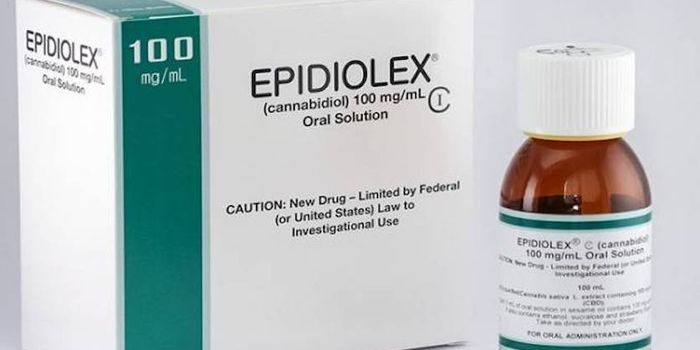

APR 04, 2019Cannabis SciencesThe cannabis plant has a myriad of chemicals within it, all of which are taken into our bodies when it is smoked or eate ...